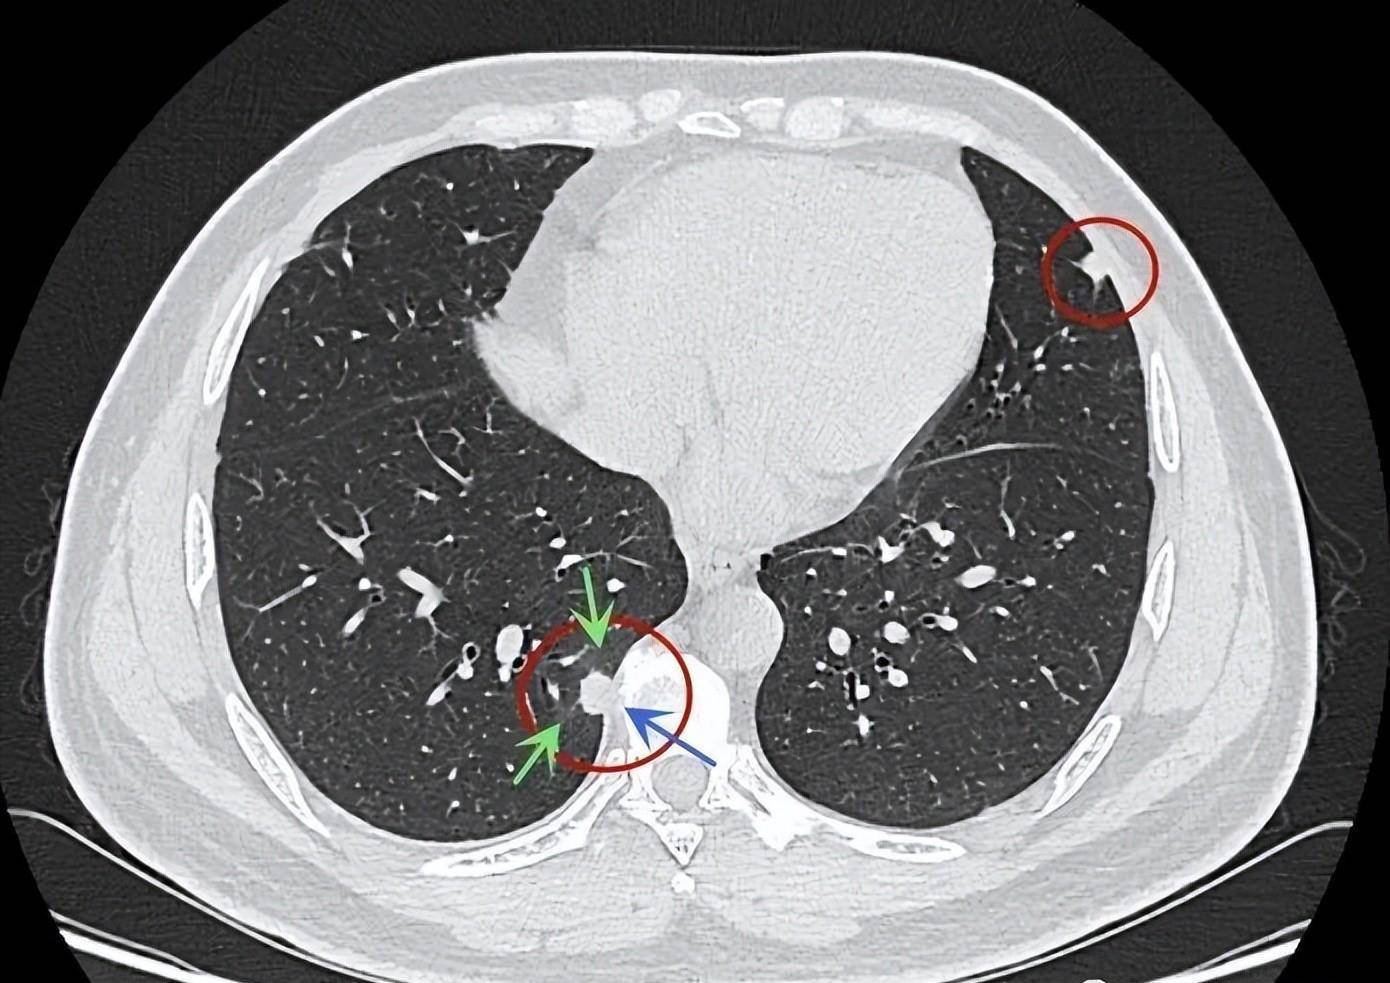

肺结节的三种分布模式